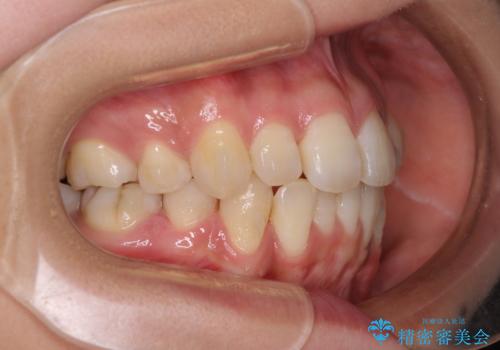

- 以前の矯正治療の後戻りにより、上下の前歯がでこぼこになってしまったことを気にして来院された患者様です。

口元がこれ以上突出することなく前歯の叢生が改善できるよう、歯と歯の間を削ってスペースを獲得し、インビザラインを用いて整えていくこととしました。

目安の装着時間である1日22時間をしっかりと実践してくださり、半年強という短期間で治療を終えることができました。